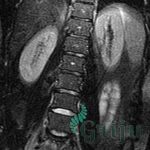

Дискогенная радикулопатия

Дискогенная радикулопатия происходит по причине развития межпозвоночной грыжи. Оболочка студенистого тела межпозвоночного диска рвется, вещество выделяется в окружающее пространство, придавливая мягкие ткани. Выделяют две степени — с разрывом фиброзного кольца и без.

В случае отсутствия разрыва (протрузии межпозвоночного диска) фиброзное кольцо становится тоньше. Студенистое тело увеличивается свое давление, приводя к сдавливанию корешка. В случае грыжи — фиброзное кольцо разрывается, вещество выделяется в пространство. Кроме корешка, может быть поврежден спинной мозг и окружающие его мышцы.